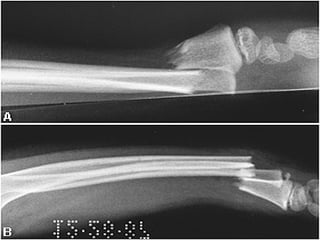

ESTUDIOS RADIOGRAFICOS SIMPLES Corroboran la presencia de Fx. Permiten darse cuenta de la lesión de partes blandas La localización de la Fx. Tipo de trazos de la Fx. Numero de fragmentos El desplazamiento La presencia o ausencia de una patología

EXTENSION Completa Incompleta (fisuras, abombamiento y tallo verde

ESTUDIOS RADIOGRAFICOS SIMPLESCorroboran la presencia de Fx. Permiten darse cuenta de la lesión de partes blandas La localización de la Fx. Tipo de trazos de la Fx. Numero de fragmentos El desplazamiento La presencia o ausencia de una patología

EXTENSION Completa Incompleta(fisuras, abombamiento y tallo verde